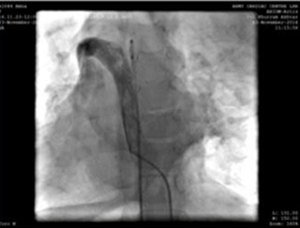

La vena femorale destra e l'arteria sono state cannulate utilizzate 5F guaina radiale. Durante la procedura, abbiamo trovato la vena cava inferiore (IVC) per drenare attraverso la continuazione azigosa nella vena cava superiore destra e quindi tracciare attraverso il seno coronarico dilatato nell'atrio destro. È stata presa la decisione di eseguire la procedura dalla vena giugulare interna sinistra (accessibile con guaina radiale 5F).

Puntura della vena giugulare sinistra e catetere angiografico 5F, che mostra la vena superiore del braccio-percorso di connessione vena cava-atrio destro superiore.